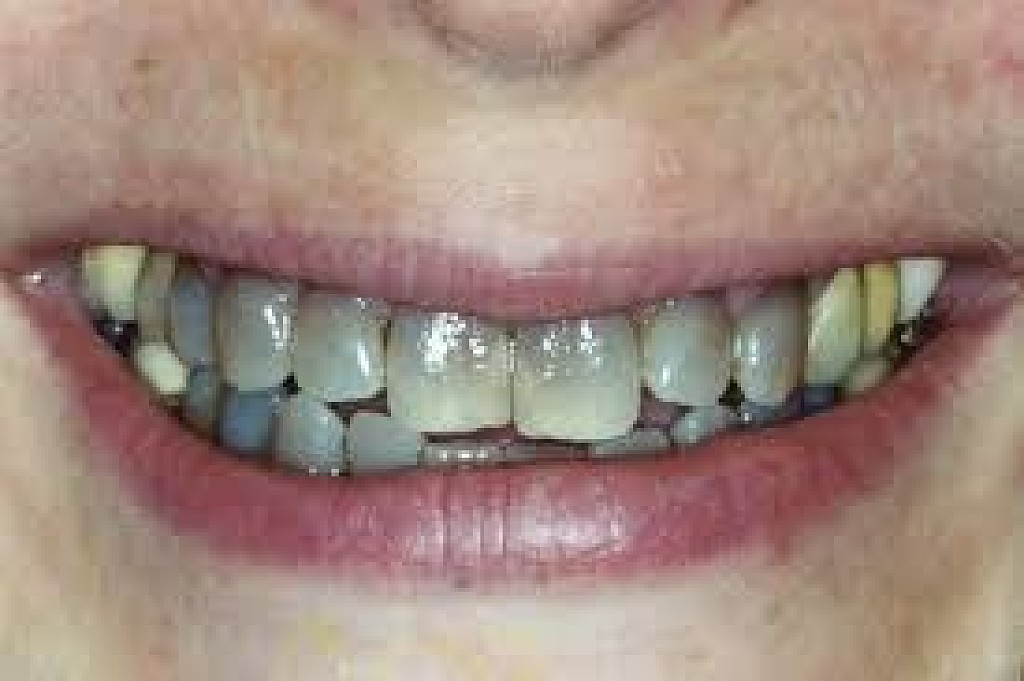

There are many reasons why a tooth can begin to go black, anything from simple staining to the death of the tooth can cause blackness and darkening.

Poor oral hygiene

Poor oral hygiene can cause your tooth to go black. In the early stages this is likely to be staining from substances like tobacco, red wine and strongly colored food. If your oral hygiene routine is not thorough enough to remove the acid-excreting bacteria each day, the acid will slowly eat away at your tooth.

As the tooth gets eaten away, tooth decay sets in. Tooth decay naturally looks black and can give the appearance of a black tooth. This gives the look of rotten teeth and is a classic result of not looking after your teeth for a considerable period of time.

The death of a tooth

When a tooth dies, the blood supply – which gives the tooth its natural, healthy color – will stop. Because the tooth is not receiving the nutrients it needs, it will begin to necrotise, darken, die and slowly go black.

Will my tooth go black after root canal?

A common misconception is that a tooth will go black after a root canal treatment. Teeth will often go black before root canal treatment as the tooth rots and decomposes on the inside. If root canal treatment is done well, all of the decomposing tissue will be removed and the blackness will not get worse. There may, however, be some mild darkening of the tooth after a root canal, depending on exactly how the root canal treatment is done and with which material.

How long does it take for a tooth to go black?

If the cause of the blackness is due to tooth decay, the blackness can happen over a period of years. If the cause of the blackness is due to trauma, as soon as the blood supply has been cut off from the tooth, the internal tooth tissue will begin to die and turn black.

Will a dead tooth go black?

If a dead tooth is left untreated, it will go black as the internal tooth tissue dies and decomposes. If the dead tooth has been root treated with a tooth-colored treatment, the tooth may not go completely black, although it may darken slightly.